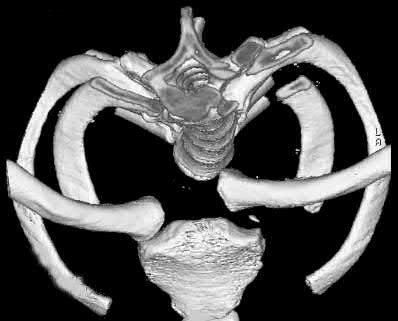

A 45-year-old male is involved in a high-speed motor vehicle collision and presents with the cervical spine radiograph findings typical of traumatic spondylolisthesis of the axis. Which of the following describes the primary mechanism of injury for this specific fracture pattern (Hangman's fracture)?

Correct Answer: Hyperextension and axial loading

Explanation:

A 'Hangman's fracture' is a traumatic spondylolisthesis of the axis (C2) involving fractures through the pars interarticularis. The classical mechanism of injury in modern trauma (e.g., unrestrained passenger hitting the windshield) is hyperextension and axial loading. Flexion-distraction typically causes Chance fractures, while flexion-compression typically causes anterior wedge or teardrop fractures.